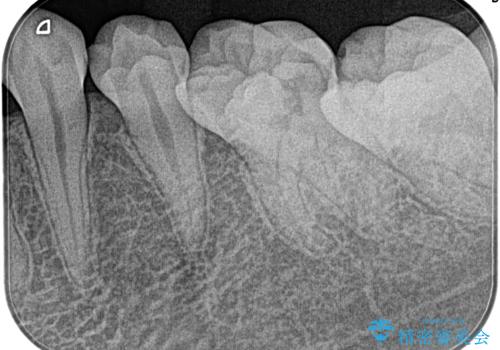

- 1週間前から左下奥がズキズキして、冷たいもので激痛を主訴に来院されました。

不可逆性歯髄炎の診断のもと根管治療を行なっております。